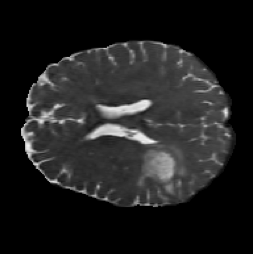

FNO Baseline (Figure 4, PDF page 8)

FNO input MRI slice.

Input MRI

DICE 65.13% · Captures global context but loses boundary precision.